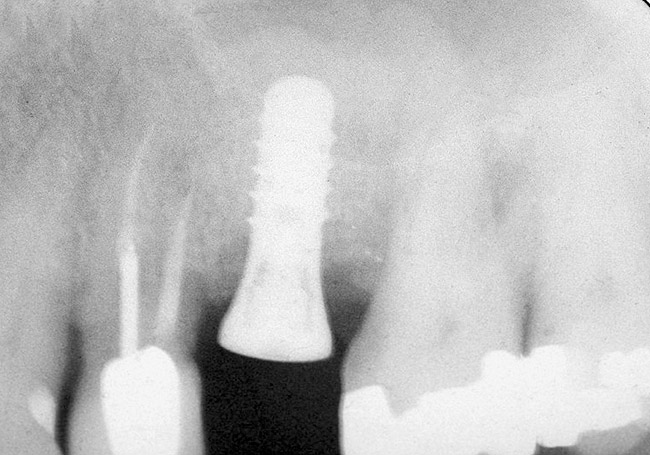

After penetration into the sinus is achieved, a sterile amalgam carrier is used two times to deliver a radiopaque bone substitute into the osteotomy. Then the osteotome used to infracture the subantral floor is lubricated with saline and inserted into the osteotomy until the stop on the osteotome reaches the alveolar crest. This pushes the bone substitute up under the sinus membrane and elevates it. Two more carriers of bone substitute are delivered in the same manner. This will provide around 2 mm of bone height in the sinus (four carriers provide around 2 mm of bone height). A radiograph is then taken to verify that the membrane was elevated, and the bone graft should appear as a dome (Figure 4). If the sinus floor has not been penetrated despite the impression that it was, the bone-graft material may have been pushed laterally. If this occurs, there will be no dome on the radiograph, but, rather, increased osseous density on the lateral aspect of the osteotomy. If this occurs the osteotomy needs to be deepened.

Figure 4  After infracturing the subantral wall with a 3.5-mm osteotome, bone was added and the presence of a dome was confirmed with a radiograph.

Figure 4